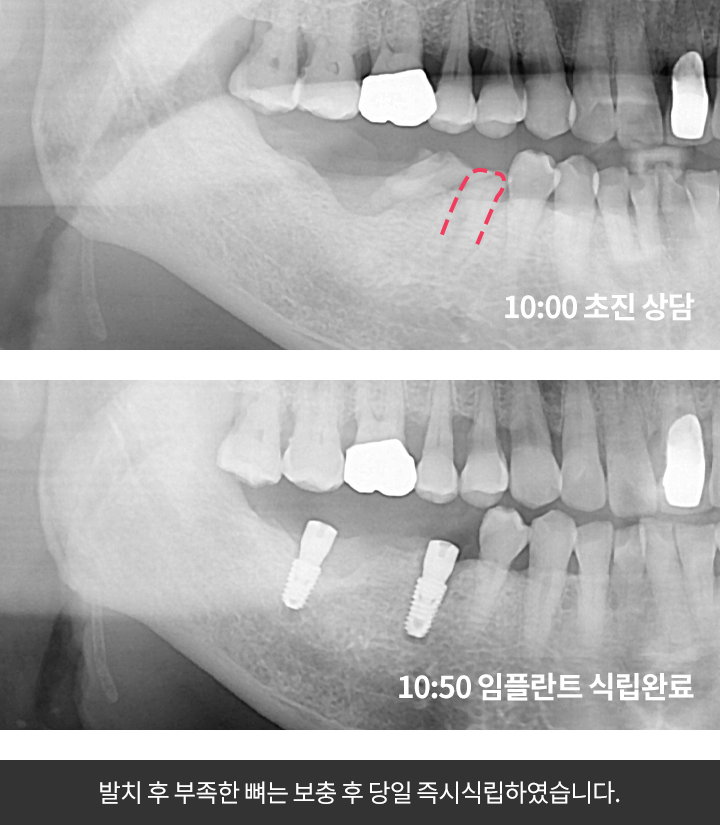

우선 CT촬영 등을 통해 구강상태를 정밀 진단 후 환자의 상태에 따라 맞는 치료 계획을 세웁니다. 구체적인 임플란트 시술 과정과 기간은 환자의 상태에 따라 달라질 수 있다고 해요.

2단계 1차 수술

이 과정은 픽스쳐를 잇몸뼈에 심는 과정인데요. (픽스쳐란 치아의 뿌리 역할을 하는 것을 말함)

이때 잇몸을 절개하는 방식과 무절개 방식 두가지가 있다고 해요.

잇몸 절개 방식은 일반적으로 많이 시술하며 잇몸을 열어 치조골에 필스쳐를 심은 뒤 절개 부위를 덮고 실로 봉합하는 방식인데요. 이 수술은 보통 1시간 정도 걸리며 수술후 1~2주뒤 수술부위가 아물면 실밥을 제거한다고 해요.

3단계 2차 수술

픽스쳐와 보철물을 견결할 공간을 만들기 위해 진행하는 수술로 잇몸밖으로 나사를 연결하는 과정인데요. 1차 수술 이후 식립한 임플란트 픽스쳐가 자연 치아의 뿌리처럼 잇몸뼈에 단단하게 고정될 때까지 기다려야하며 픽스쳐가 치조골과 단단히 결합해 안정화되어야 2차 수술을 진행할 수 있다고 해요.

그후 연결기둥인 임플란트 지대주를 부착한다고 해요.

4단계 크라운제작 및 교정

수술부위가 아물면 임플란트 지주대와 주변치아를 본을 뜬뒤, 치아 형태의 보철물인 크라운 제작을 한다고 해요. 크라운 제작 기간은 보통 일주일 정도라고 해요. 보철물이 완성되면 크라운을 임플란트 지대주에 장착해 고정시킵니다고 해요. 그 다음 음식을 씹을 때 불편함이 없도록 조정한다고 해요.

임플란트 시술과정과 시술기간은 환자의 구강 및 건강 상태에 따라 달라질 수 있다고 해요.